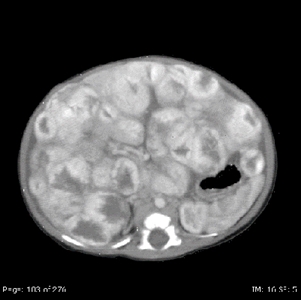

On MRI, vascular tumors of the liver are hyperintense on T2 imaging and hypointense on T1 imaging, with postcontrast imaging demonstrating early peripheral enhancement with eventual diffuse enhancement.[76] In practice, these tumors have been classified according to their clinical characteristics and radiological assessment.[76,154] In general, hepatic vascular tumors can be benign or malignant.

These lesions are usually divided into the following three categories:[76,154]